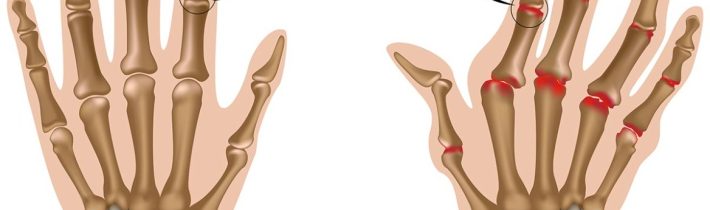

Reumatoidnú artritídu môžeme definovať ako stav, počas ktorého kĺb zostáva v neustálom zápalovom stave. Reumatoidná artritída sa väčšinou vyskytuje u starších mužov a žien a zriedkavo postihuje mladých mužov a ženy. Základná príčina reumatoidnej artritídy je stále nejasná, ale patrí do kategórie autoimunitných ochorení. Autoimunitné ochorenie je ochorenie, pri ktorom sa imunitný systém tela rozpadne a začne napádať jeho tkanivá. Nemôžeme povedať, že reumatoidná artritída je dedičné ochorenie, ale v niektorých prípadoch môže byť spôsobené dedičnými dôvodmi.

U niektorých ľudí môže toto ochorenie vyvolať viaceré príznaky. Tí pacienti, ktorí majú viaceré problémy s kĺbmi, sa môžu nechať skontrolovať na reumatoidné faktory prostredníctvom vzoriek krvi. Pomôže to pri analýze rozsahu, v akom môžu byť rôzne kĺby v krátkom čase poškodené. Kĺb postihnutý reumatoidnou artritídou bude mať opuch a hrúbku a čerstvé krvné cievy okolo neho.

RA (reumatoidná artritída) je závažná zápalová autoimunitná porucha, ktorá má za následok deformáciu, opuch, stuhnutosť a bolesť kĺbov. Môže tiež viesť k rozvoju ankylózy – stuhnutosti spôsobenej abnormálnou rigiditou a adhéziou kĺbu v dôsledku akejkoľvek choroby alebo zranenia. Táto komplexná povaha artritídy robí liečbu náročnou, pretože zahŕňa rôzne prístupy. Liečba je založená na zmiernení zápalu a prináša tak úľavu pri opuchoch a bolestiach kĺbu. To nakoniec pomáha pri zlepšovaní stavu pacienta a tiež zabraňuje akémukoľvek druhu trvalej invalidity. Ak sa reumatoidná artritída nelieči včas, môže viesť k ťažkej invalidite, funkčným obmedzeniam a chronickej deštrukcii kĺbov.